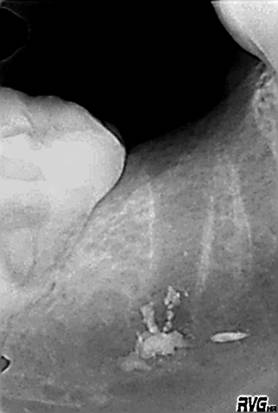

На ОРТПГ и RVG, в области отсутствующего 47зуба, наблюдается инородное тело, рентгеноконтрастное, с чёткими границами, неопределённой формы, размером 0,5/0,5 см (предположительно пломбировочный материал), находящееся в проекции нижнечелюстного канала, в области верхушки дистального корня, раннее удалённого 47зуба.

Под местной анестезией Sol.Ultracaini DS 2,5 ml, сделан разрез по переходной складке, в проекции 46, 47,48 зубов, отслоен и мобилизован слизисто-надкостничный лоскут. Сделано перфорационное отверстие в проекции верхушек корней 47зуба, размером 1.8/1.0 см, с удалением наружного кортикального и части губчатого слоя. Обнаружено наличие кусочков пломбировочного материала, при прикосновении к которым, наблюдалось свободное продвижение их по самому нижнечелюстному каналу, что в свою очередь затруднило извлечение данного пломбировочного материала. Тем не менее, под контролем микроскопа, были удалены все кусочки материала, без повреждения сосудисто-нервного пучка. Полость кости орошена изотоническим раствором, заложена гемостатическая губка, рана ушита Викрилом.